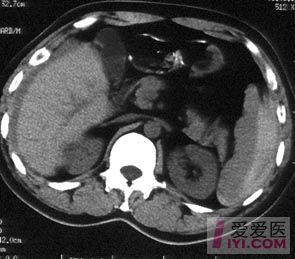

脾破裂CT

脾脏破裂,周围积血.

原创经典ct图片脾破裂